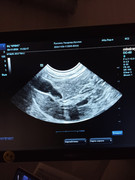

Сделали повторное узи 22.11. 2024 (первое было 09.11.2024). Высылаю фото и заключение.

Теперь ставят гидрометру и эндометрит. По мочевому мочекаменную.